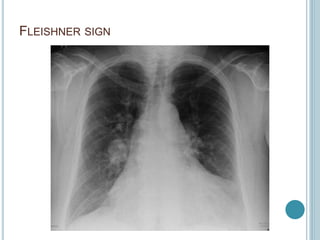

CHEST X-RAY

 Fleishner sign

 Hampton hump

 Westermark sign

FLEISHNER SIGN